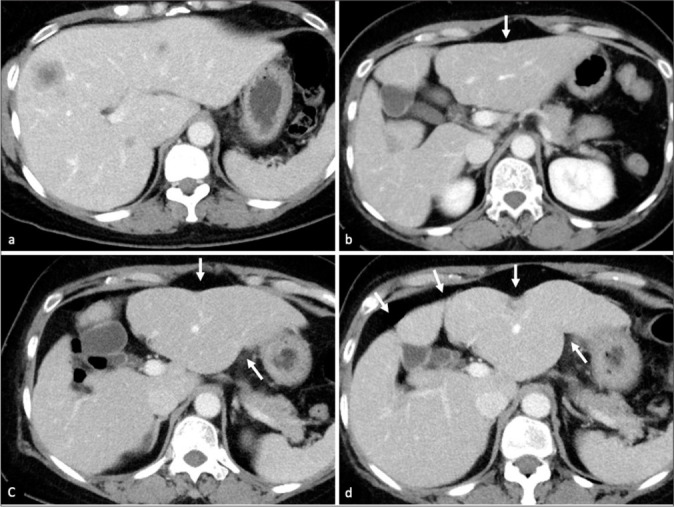

在过去的几十年里,化疗的使用彻底改变了癌症的治疗。肝毒性在不同类型的化疗药物中普遍存在。这篇图片综述的目的是阐明各种化疗相关肝实质改变在不同成像方式下的放射学特征,并通过代表性病例展示这些肝损伤模式的潜在并发症。早期识别这些肝脏疾病可以及时采取临床行动,从而优化管理并避免严重并发症。

The use of chemotherapy has revolutionized the management of cancer in the past decades. Liver toxicity is commonly observed among different types of chemotherapy drugs. The aim of this pictorial review is to illustrate radiological features of various chemotherapy-associated hepatic parenchymal changes in different imaging modalities and to demonstrate potential complications of these liver injury patterns with representative cases. Early recognition of these liver conditions allows prompt clinical action to be taken, thus optimizing management and avoiding severe complications.